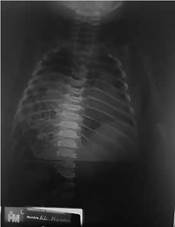

Se realiza radiografía de tórax que muestra hallazgos compatibles con HDC derecho (Fig. 1).

Figura 1. Ocupación de hemitórax derecho de contenido intestinal, con desplazamiento de mediastino hacia la región contralateral